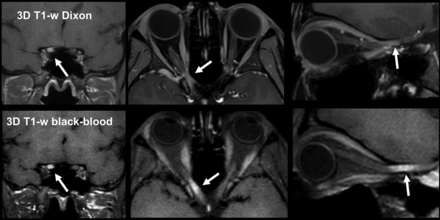

MR imaging of a 27-year-old female patient with symptoms of acute optic neuritis of the right eye with retrobulbar pain and loss of vision for 4 days. Images of a contrast-enhanced 3D T1-weighted Dixon sequence are shown in the upper row, and contrast-enhanced 3D T1-weighted BB images, in the lower row with coronal, axial, and sagittal reconstructions. Note the enhancing lesion in the right optic nerve in the extraorbital section (arrows) with improved contrast depiction in the contrast-enhanced 3D T1-weighted BB sequence compared with the contrast-enhanced 3D T1-weighted Dixon imaging.